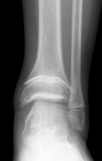

| SH I distal tibia / fibula | SH II distal tibia | SH III medial malleolus |

| Low risk growth arrest | 40% risk growth arrest | 30% risk physeal bar |